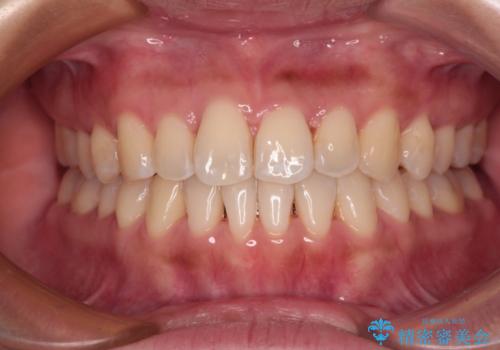

[ マウスピース矯正 ] 長期海外出張中に矯正治療を行いたい

![[ マウスピース矯正 ] 長期海外出張中に矯正治療を行いたいの症例 治療後](https://seimitsushinbi.jp/wp/wp-content/uploads/2023/04/IMG_0020-500x350.jpg?v=1682416167)